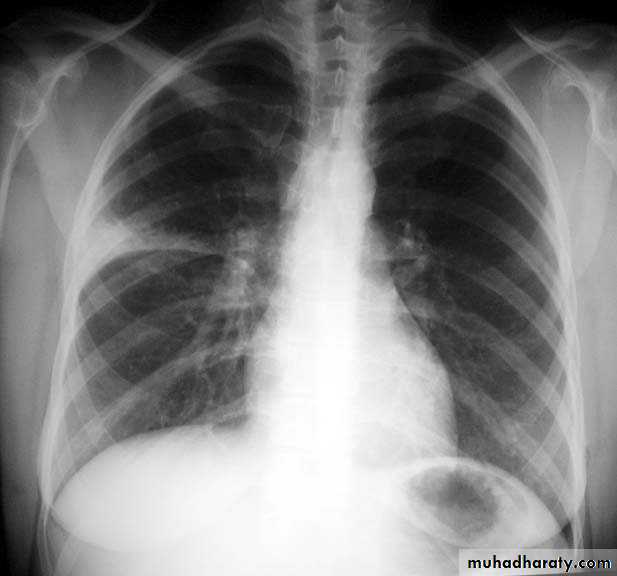

Encysted peural effusion

Sub costalFissural

Sub pulmonary